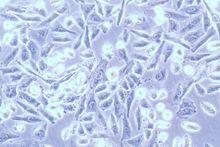

二倍體細胞株來源於正常人胎兒組織,主要用於培養病毒製備疫苗等。

1.4 細胞培養史和生長特徵,細胞壽命、世代數。

細胞原系建株過程,每8~12世代*應作一次染色體檢查,一株細胞整個生命期內連續培養過程中,至少應有4~5次染色體檢查結果。

每次染色體檢查,應從同一世代不同細胞培養瓶中取細胞混合再培養,製備染色體標本片。染色體標本應長期保存(直至褪色不能用為止),以備複查。

二倍體細胞每次染色體檢查,至少應隨機取1000個分裂中期細胞,進行染色體數目、形態和結構檢查,並作出有助於複查的記錄,其中至少選擇50個分裂中期細胞進行顯微照相,作出核型分析。並應粗數500個分裂中期細胞,檢查多倍體的發生率。